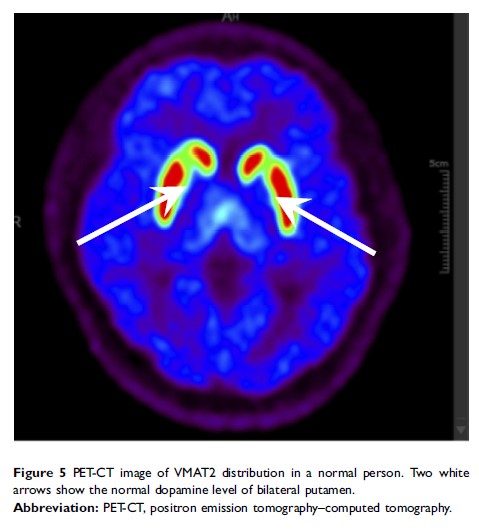

帕金森病的冻结现象与黑质纹状体系统的多巴胺水平下降和视觉皮层损害有关